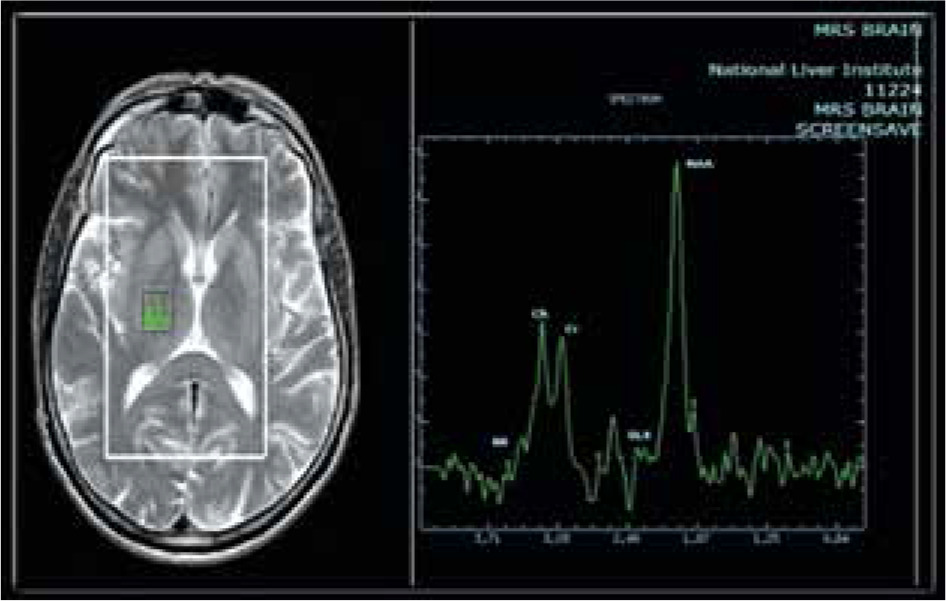

The MRS characteristics in the basal ganglia or thalamus demonstrated an increase in the brain metabolite Glx with a significant correlation to the presence and grade of HE, as we found its presence with low amounts in the control group, whereas in overt HE, we found large amounts of Glx in the brain with a significant difference (p = 0.001). Other brain metabolites, such as Cho and mI, were present in large quantities in the control group, as shown in Figure 1, which displayed a normal MRS evaluation spectrum. However, in the overt HE groups, we observed a significant decline in their quantities (p = 0.001). Two brain metabolites (NAA and Cr) were not significantly different between all grades of HE and the control groups (p = 0.47 and 0.38, respectively) (Table 3, Fig. 2).

Fig. 2

Magnetic resonance spectroscopy (MRS) in: A) a healthy patient, B) a cirrhotic patient with minimal hepatic encephalopathy (MHE), and C) a cirrhotic patient with overt HE showing increase of glutamate/glutamine complex (Glx) in cirrhotic patient with MHE and marked increase of Glx in cirrhotic patients with overt HE, decrease of myoinositol and choline values in cirrhotic patient with MHE and marked decrease in cirrhotic patient with overt HE. The region of interest (ROI) was located in the thalamus on MRS